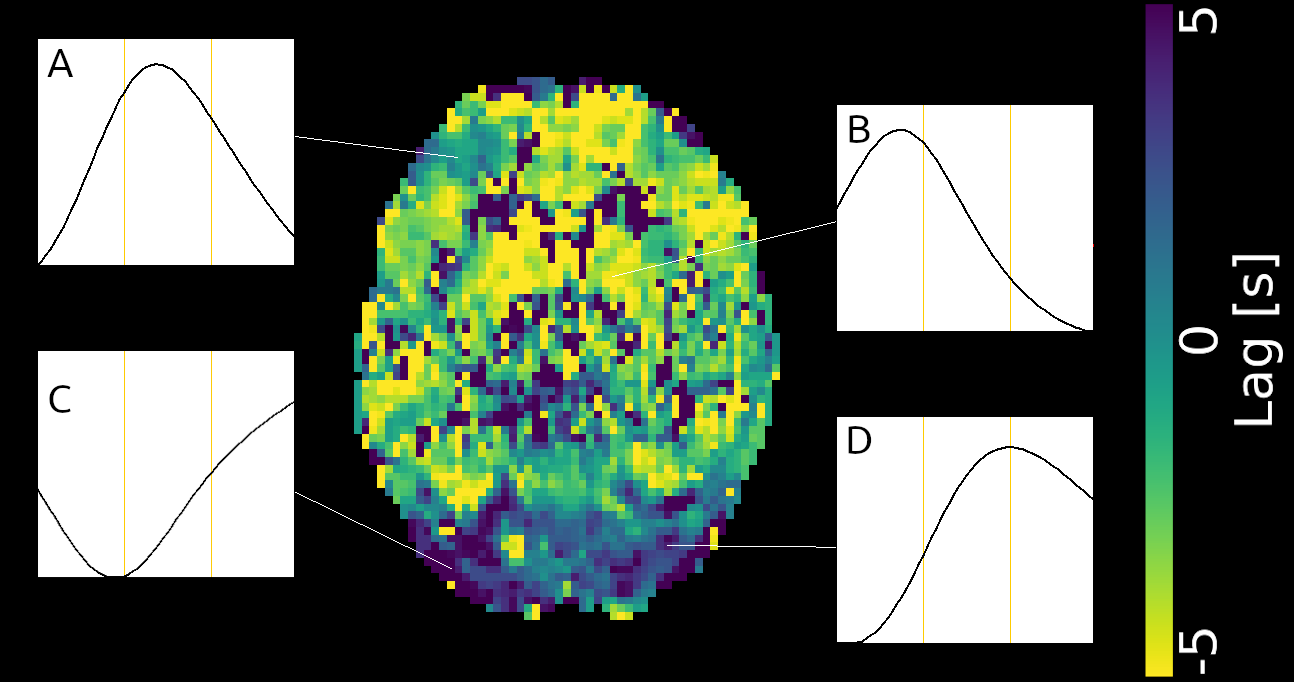

Lag optimisation

Different methods have been proposed to take into account the lag of CVR:

cross-correlation (RIPTiDe)¹,

Lagged GLM (L-GLM)²,

bayesian estimation³, ...

An important factor to take into account is to set up denoising and CVR estimation simultaneously⁴

CVR estimates optimisation

Different methods have been proposed to take into account the lagged CVR:

- RIPTiDe: cross-correlation (X-corr)¹

- Lagged GLM after orthogonalising signal of interest to noise²

Methods: CVR and lag maps

CVR and lag maps: L-GLM with each lagged regressor and nuisance regressors (12 motion parameters and low frequency trends), voxelwise selection of the lagged model with highest explained variance (R²), normalisation to MNI152 template (2.5 mm isotropic)

Non optimising leads to underestimate the CVR, especially in subcortical areas.

Lag maps show anatomical consistency

Different lag responses, coherent with previous evidence (e.g. Putamen has earlier response than GM)